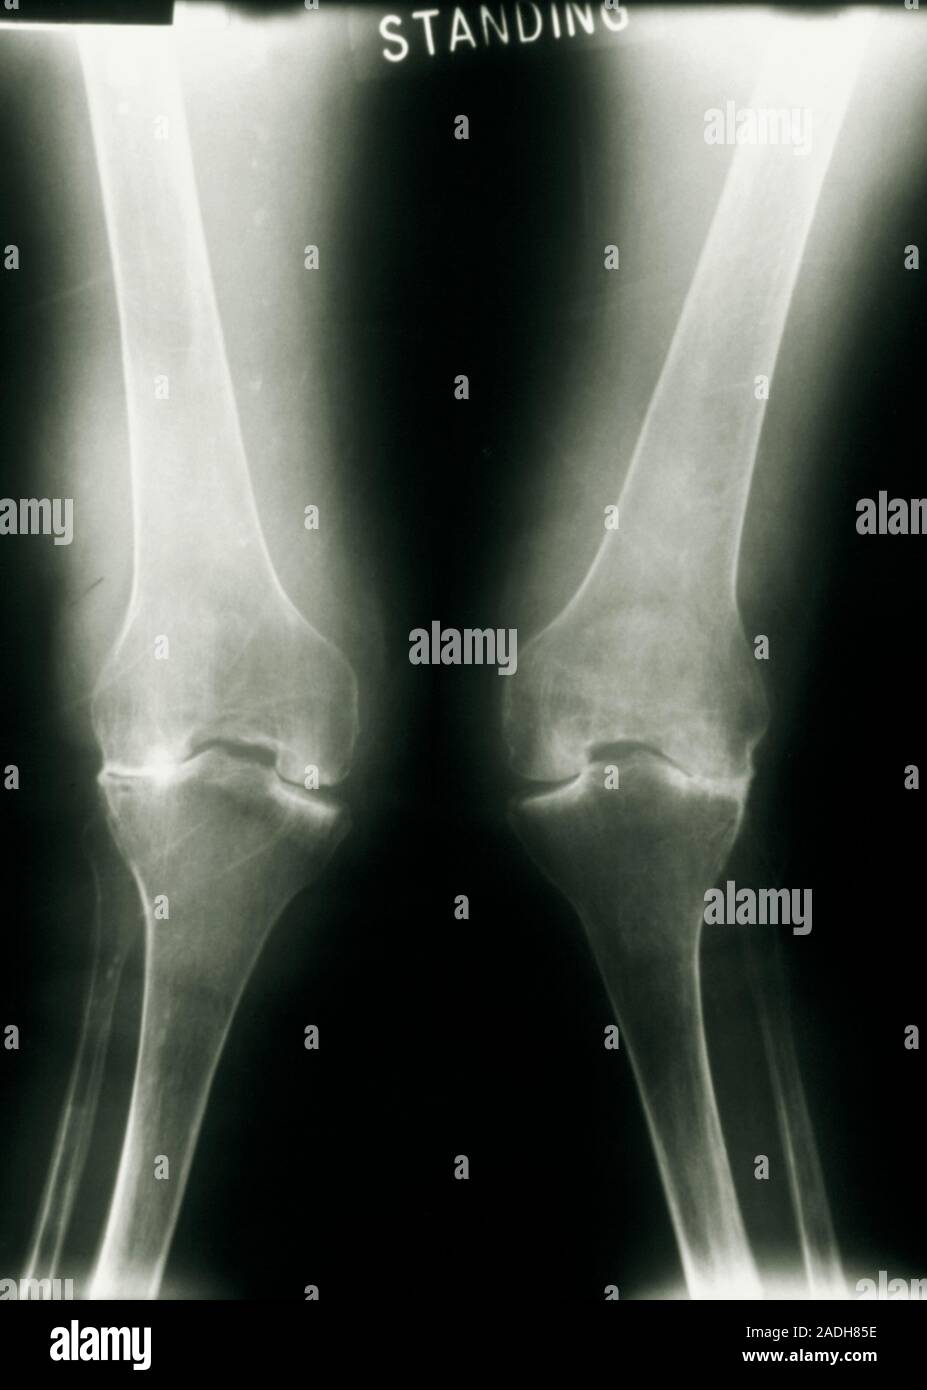

Arthritic knees. Xray showing deformation of the knees caused by Can Osteoarthritis Cause Knock Knees Knock knees in children is a normal part of growth and development, and it usually gets better as. knock knees can cause knee pain in adults. causes of knock knees. Oa can affect any joint in. it's a common issue, with estimates suggesting that almost half of all adults will develop osteoarthritis of the knee at some. Can Osteoarthritis Cause Knock Knees.